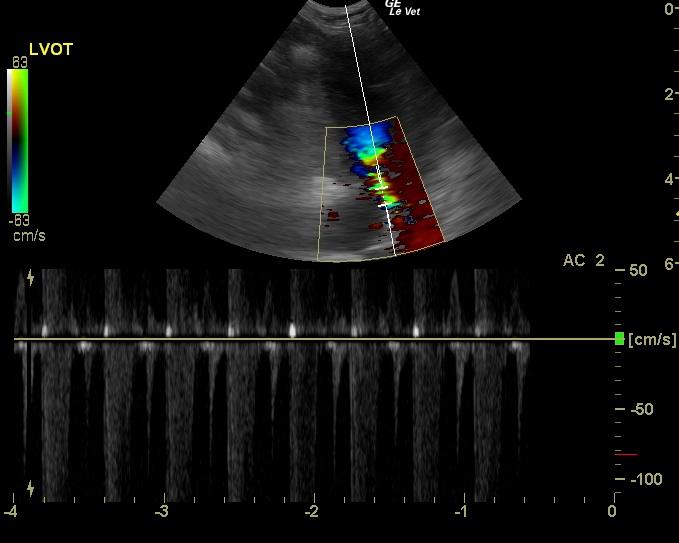

A 1-year-old intact male DSH was presented for anorexia over a 1-2 day period. Abnormalities on physical examination included hypothermia, a grade IV/VI systolic murmur, and ataxia. Leukocytosis was present on CBC. On survey radiographs, the intestines appeared to be bunched.